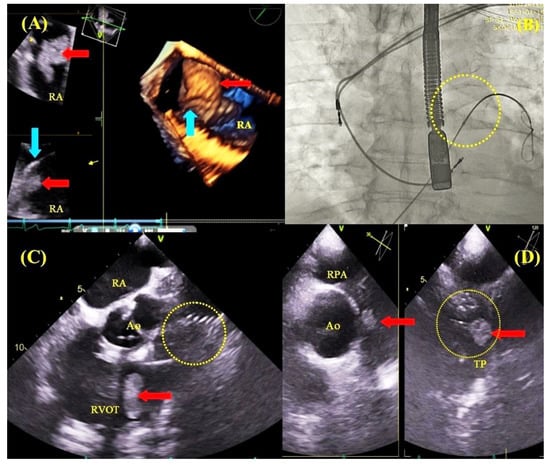

2.3. Transesophageal Echocardiographic Monitoring